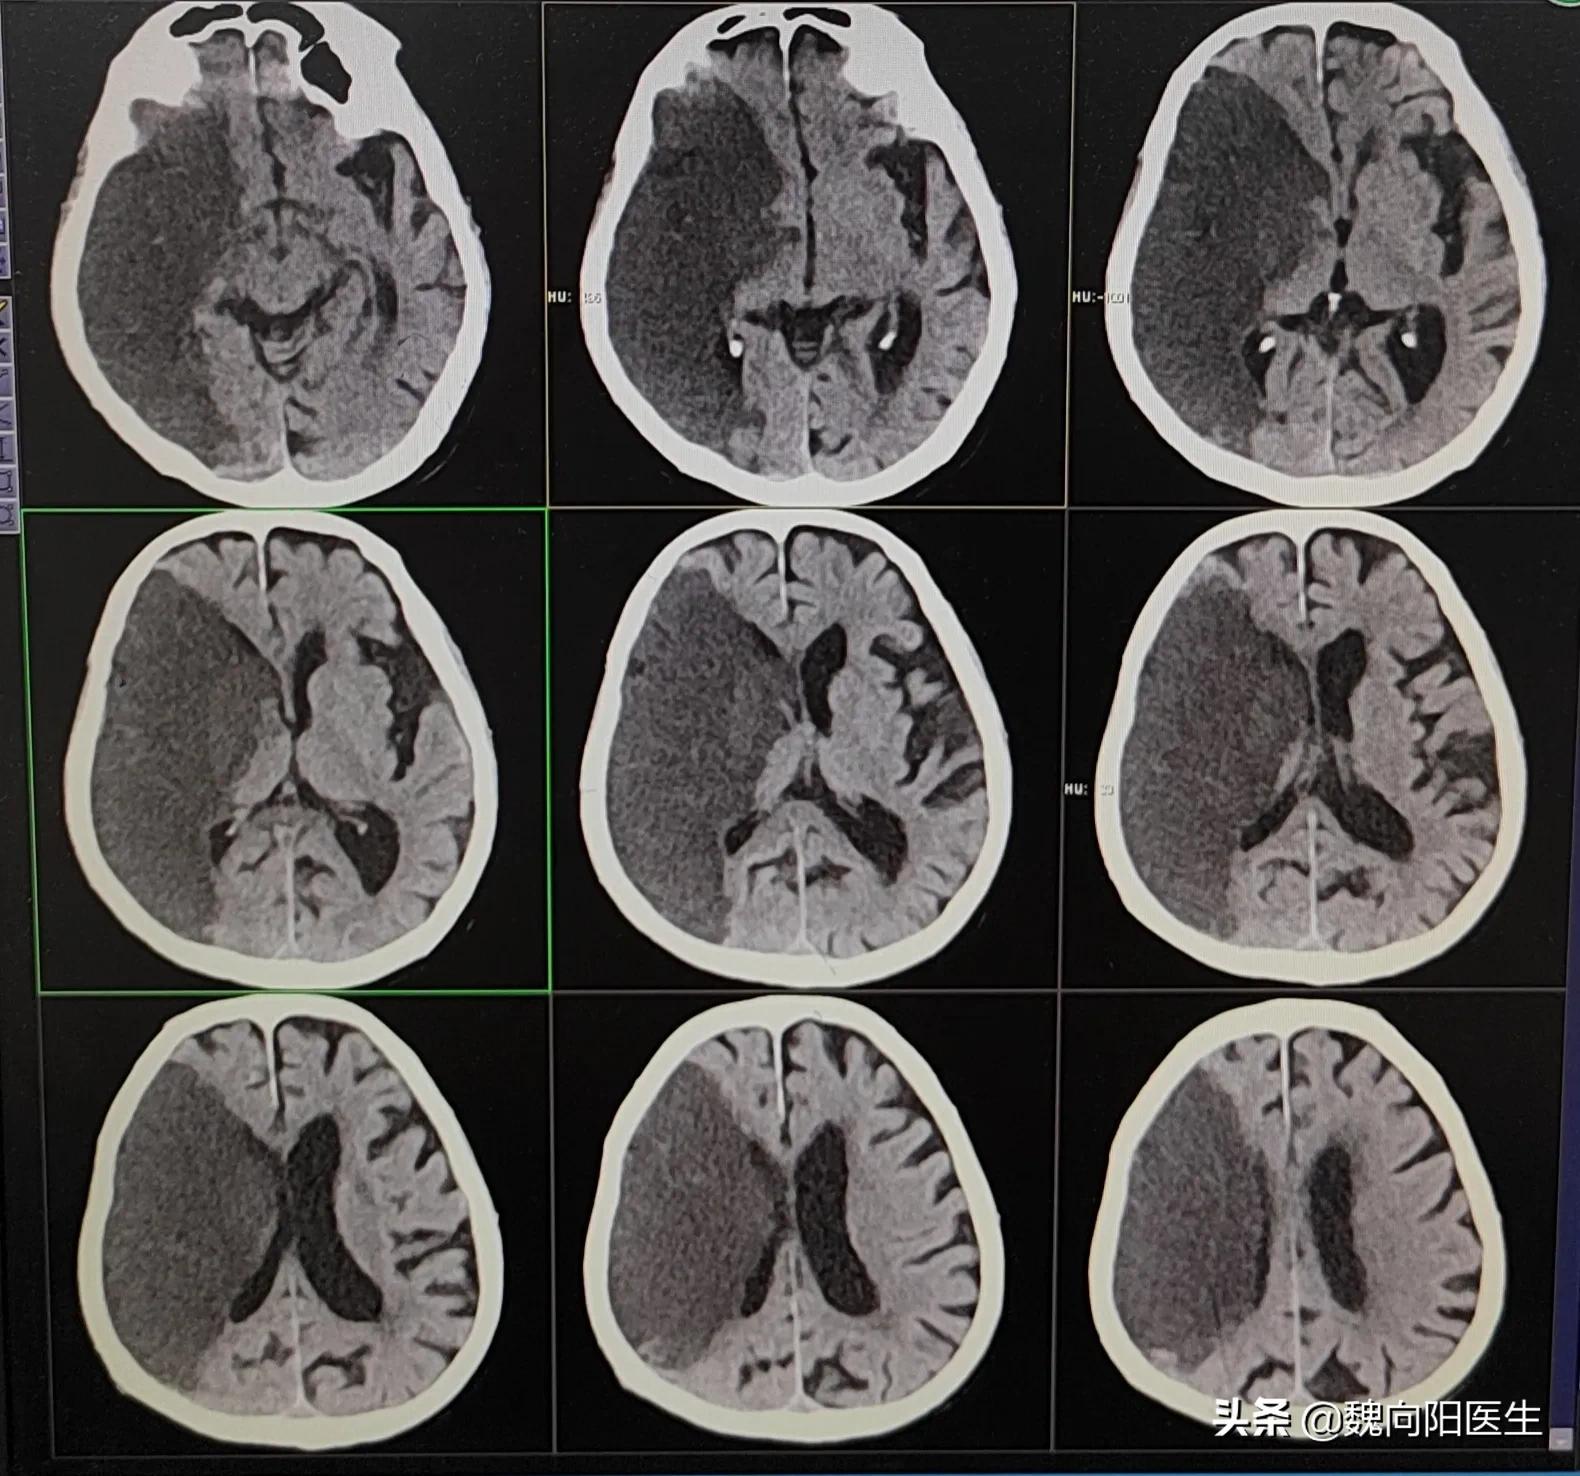

这是一个80多岁的老年患者,因为大面积脑梗塞入住医院,因为患者住院之后,意识欠清楚,不能自主进食。

重型颅脑创伤、脑出血、大面积脑梗死都是应激性溃疡的诱发因素。

因此,这个患者的胃出血,考虑是由于大面积脑梗死导致的应激性胃溃疡。与下不下胃管根本没有关系。